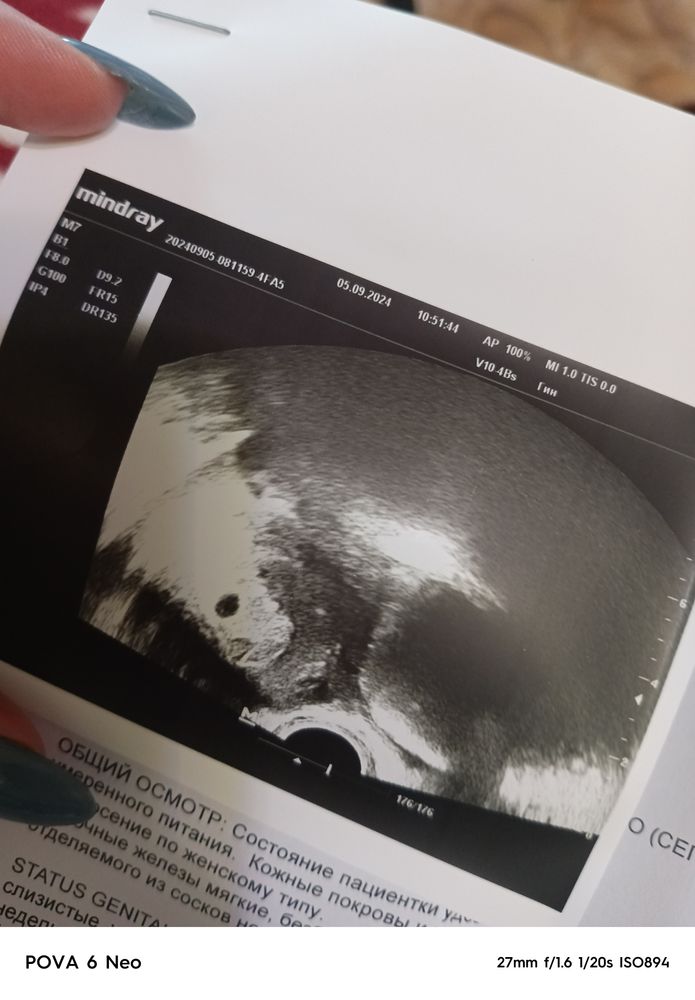

20 ДПП. Вот и сходили на УЗИ🤗 ПЯ в матке средний внутренний диаметр 7,5мм, соответствует сроку 5 недель и 5 дней, внутрений зев закрыт, гиматом и отслоек нет, хорион прекрасный 4,1. Повторное УЗИ и прослушевание сердцебиения 16.09🥰